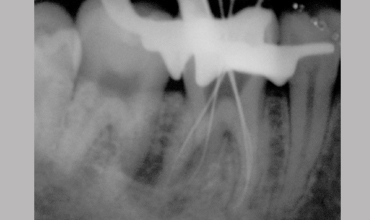

Management Of Radix Entomolaris In Mandibular First Molar